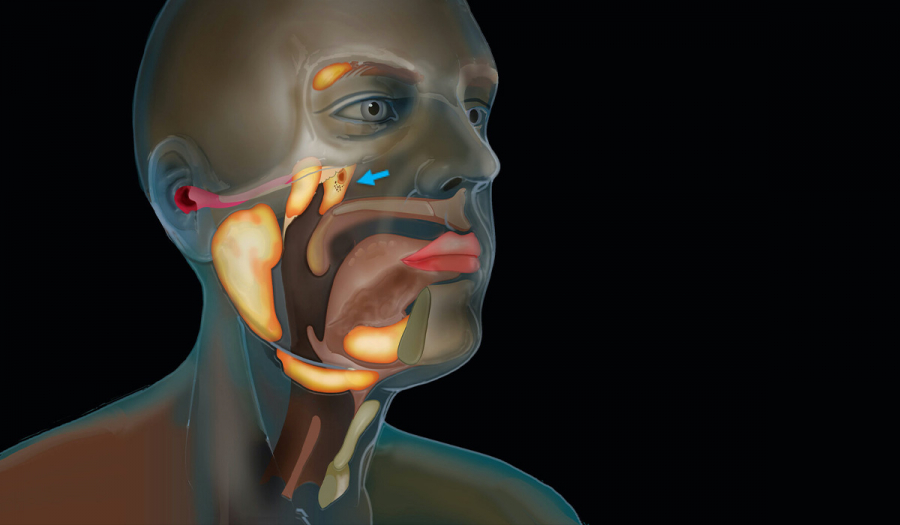

Слинні залози у нашому організмі відповідальні за вироблення слини – рідини, яка важлива для травлення та очищення порожнини рота, захисту зубів від мікроорганізмів. Однак у них можливі запальні процеси, утворення різного ступеня інтенсивності та вираженості.